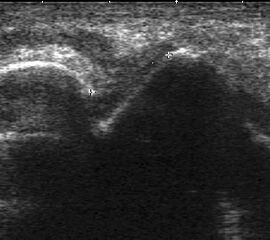

Ruptur Lig. fibulocalcaneare

Längsschnitt über dem Lig. fibulocalcaneare. Die Peronealsehnen erscheinen als echoreiche runde bis ovaläre Struktur.

Abbildung 19

Lagerung: Rückenlage, OSG in Neutralstellung.

Schnittebene: LS über Lig. fibulocalcaneare.

Referenzstrukturen: Fibulaspitze und Talus.

Befunde: Das Lig. fibulocalcaneare is nativ schlecht abgrenzbar, da es in die Tiefe und nicht parallel zum Schallkopf verläuft. Direkt über das Band ziehen quer getroffen die Peronäussehnen. Durch die Distorsion kann auch das Peritendineum peroneale einreißen. Die Peronealsehnen sind dann in ihrer Sehnenscheide von Blut umgeben, was sich als echoarmer Ring (Halo-Phänomen) darstellt und ein indirektes Zeichen für eine Verletzung des Lig. fibulocalcaneare ist.